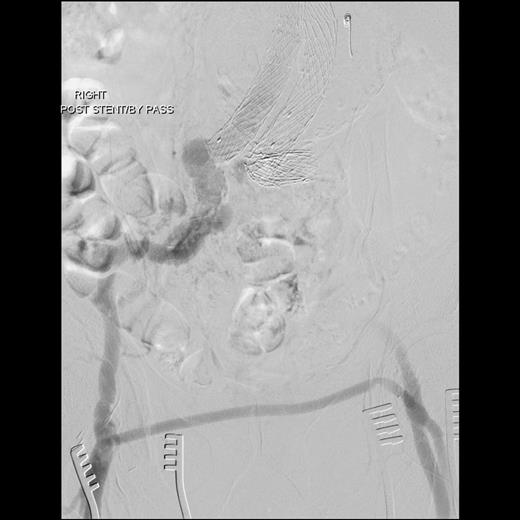

Surgery was performed in hybrid operating theatre. The aorta was accessed via bilateral groin cut-downs to expose both common femoral arteries. Intra-operatively, the type IIIa endoleak was excluded using a right-sided Cook aortouniiliac stent graft (AX1-1-36-116). The left renal arteries were cannulated from the left brachial artery. A PTFE-covered nitinol stent (Atrium V12) was advanced into the left renal artery and deployed in a chimney fashion. The left iliac limb of the stent was occluded using a 20 mm Amplatzer plug proximally and distally with Iliac Plug Zip 24 and 30 mm. Femorofemoral crossover bypass was then performed to complete the surgery. The completion angiography showed adequate sealing with no endoleak (Figs 2 and 3).

The completion angiography showed adequate sealing with no endoleak.